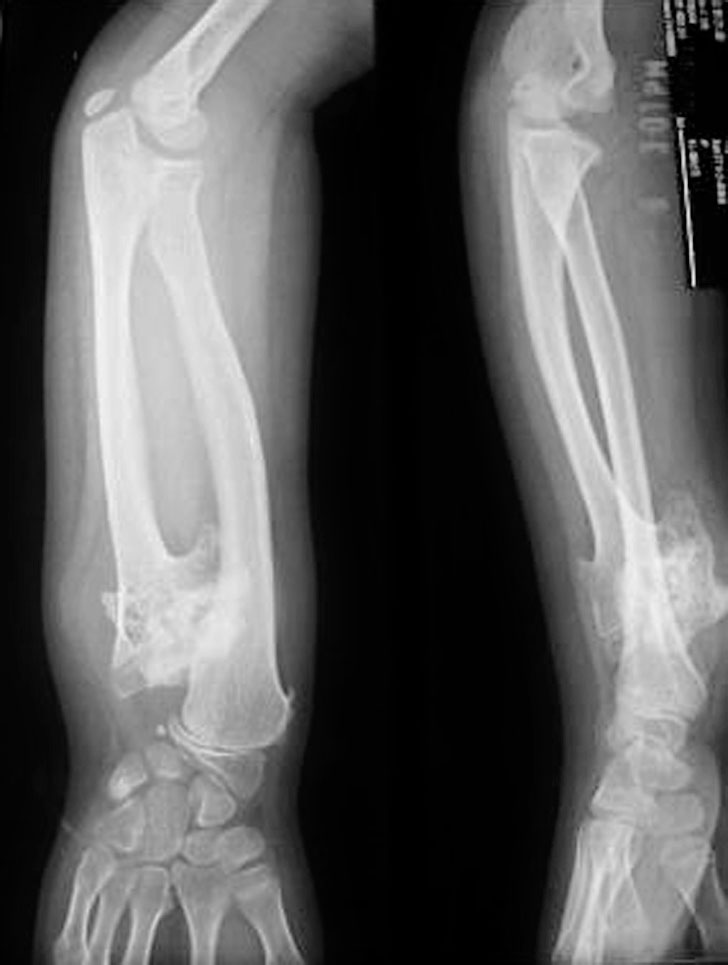

图1-2-4 桡骨部分缺如病例

X 线片显示右侧桡骨远端部分缺如,尺骨短粗,拇指漂浮拇

图1-2-5 桡骨完全缺如病例

A.右侧前臂桡侧纵列发育不良,拇指完全缺如;B.X 线片显示桡骨完全缺如,腕关节极度桡偏、脱位